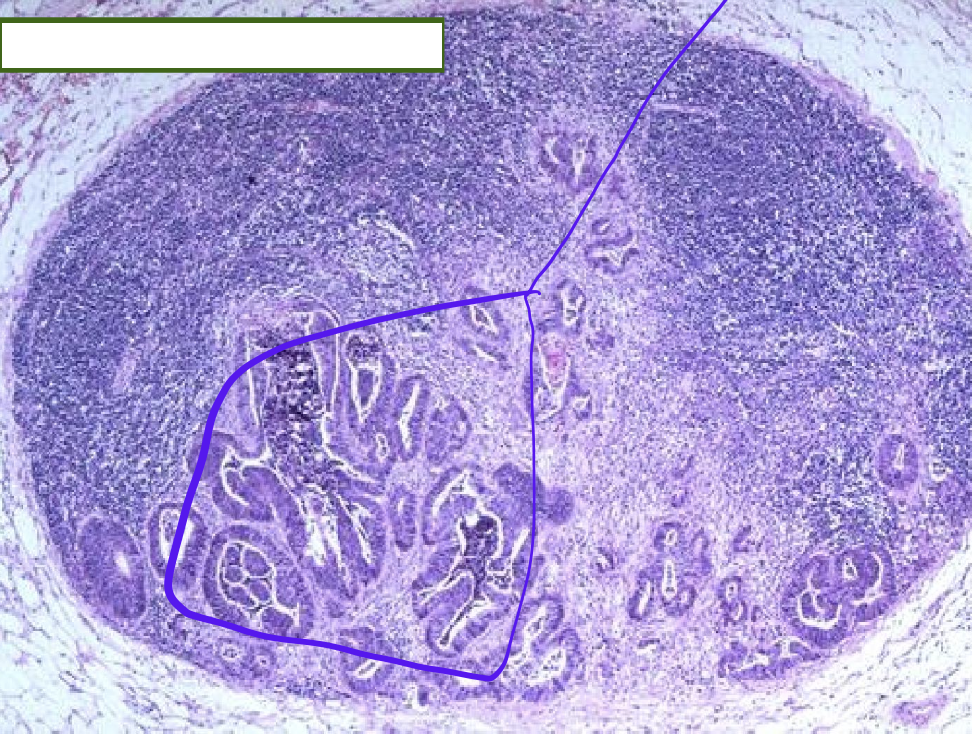

Identify the organ and the diagnosis in this format: diagnosis, organ

metastatic carcinoma, lymph node